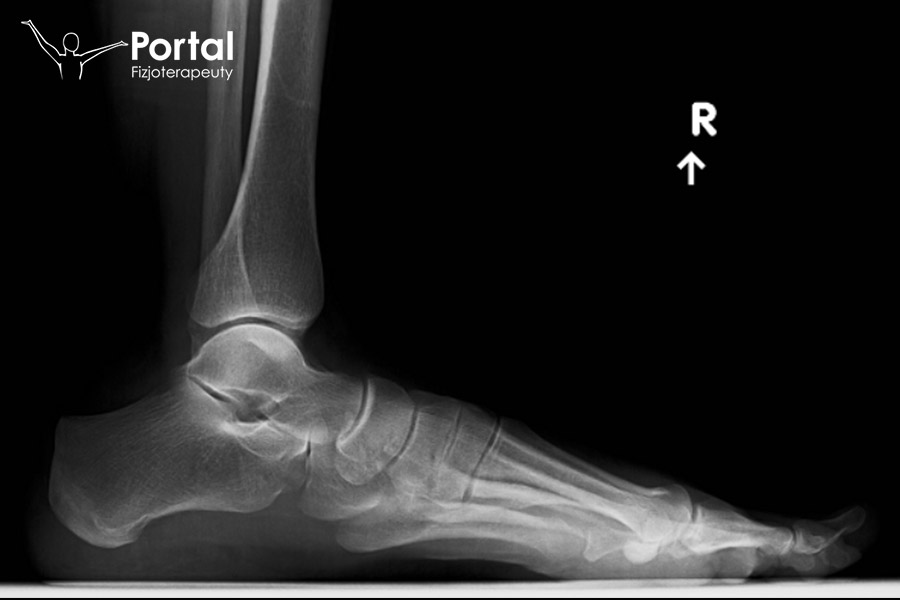

Ból w pięcie

Ból w pięcie to nieprzyjemna dolegliwość, która może mieć wiele różnych przyczyn. Zawsze wymaga wnikliwej diagnostyki i wdrożenia odpowiedniej terapii,